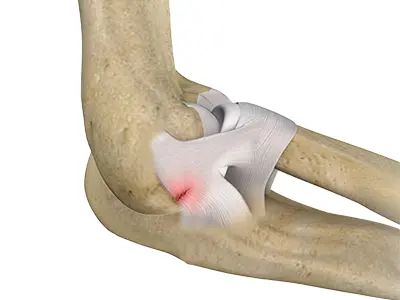

Total Elbow Replacement

Elbow joint replacement, also referred to as total elbow arthroplasty, is an operative procedure to treat the symptoms of arthritis that have not responded to non-surgical treatments.